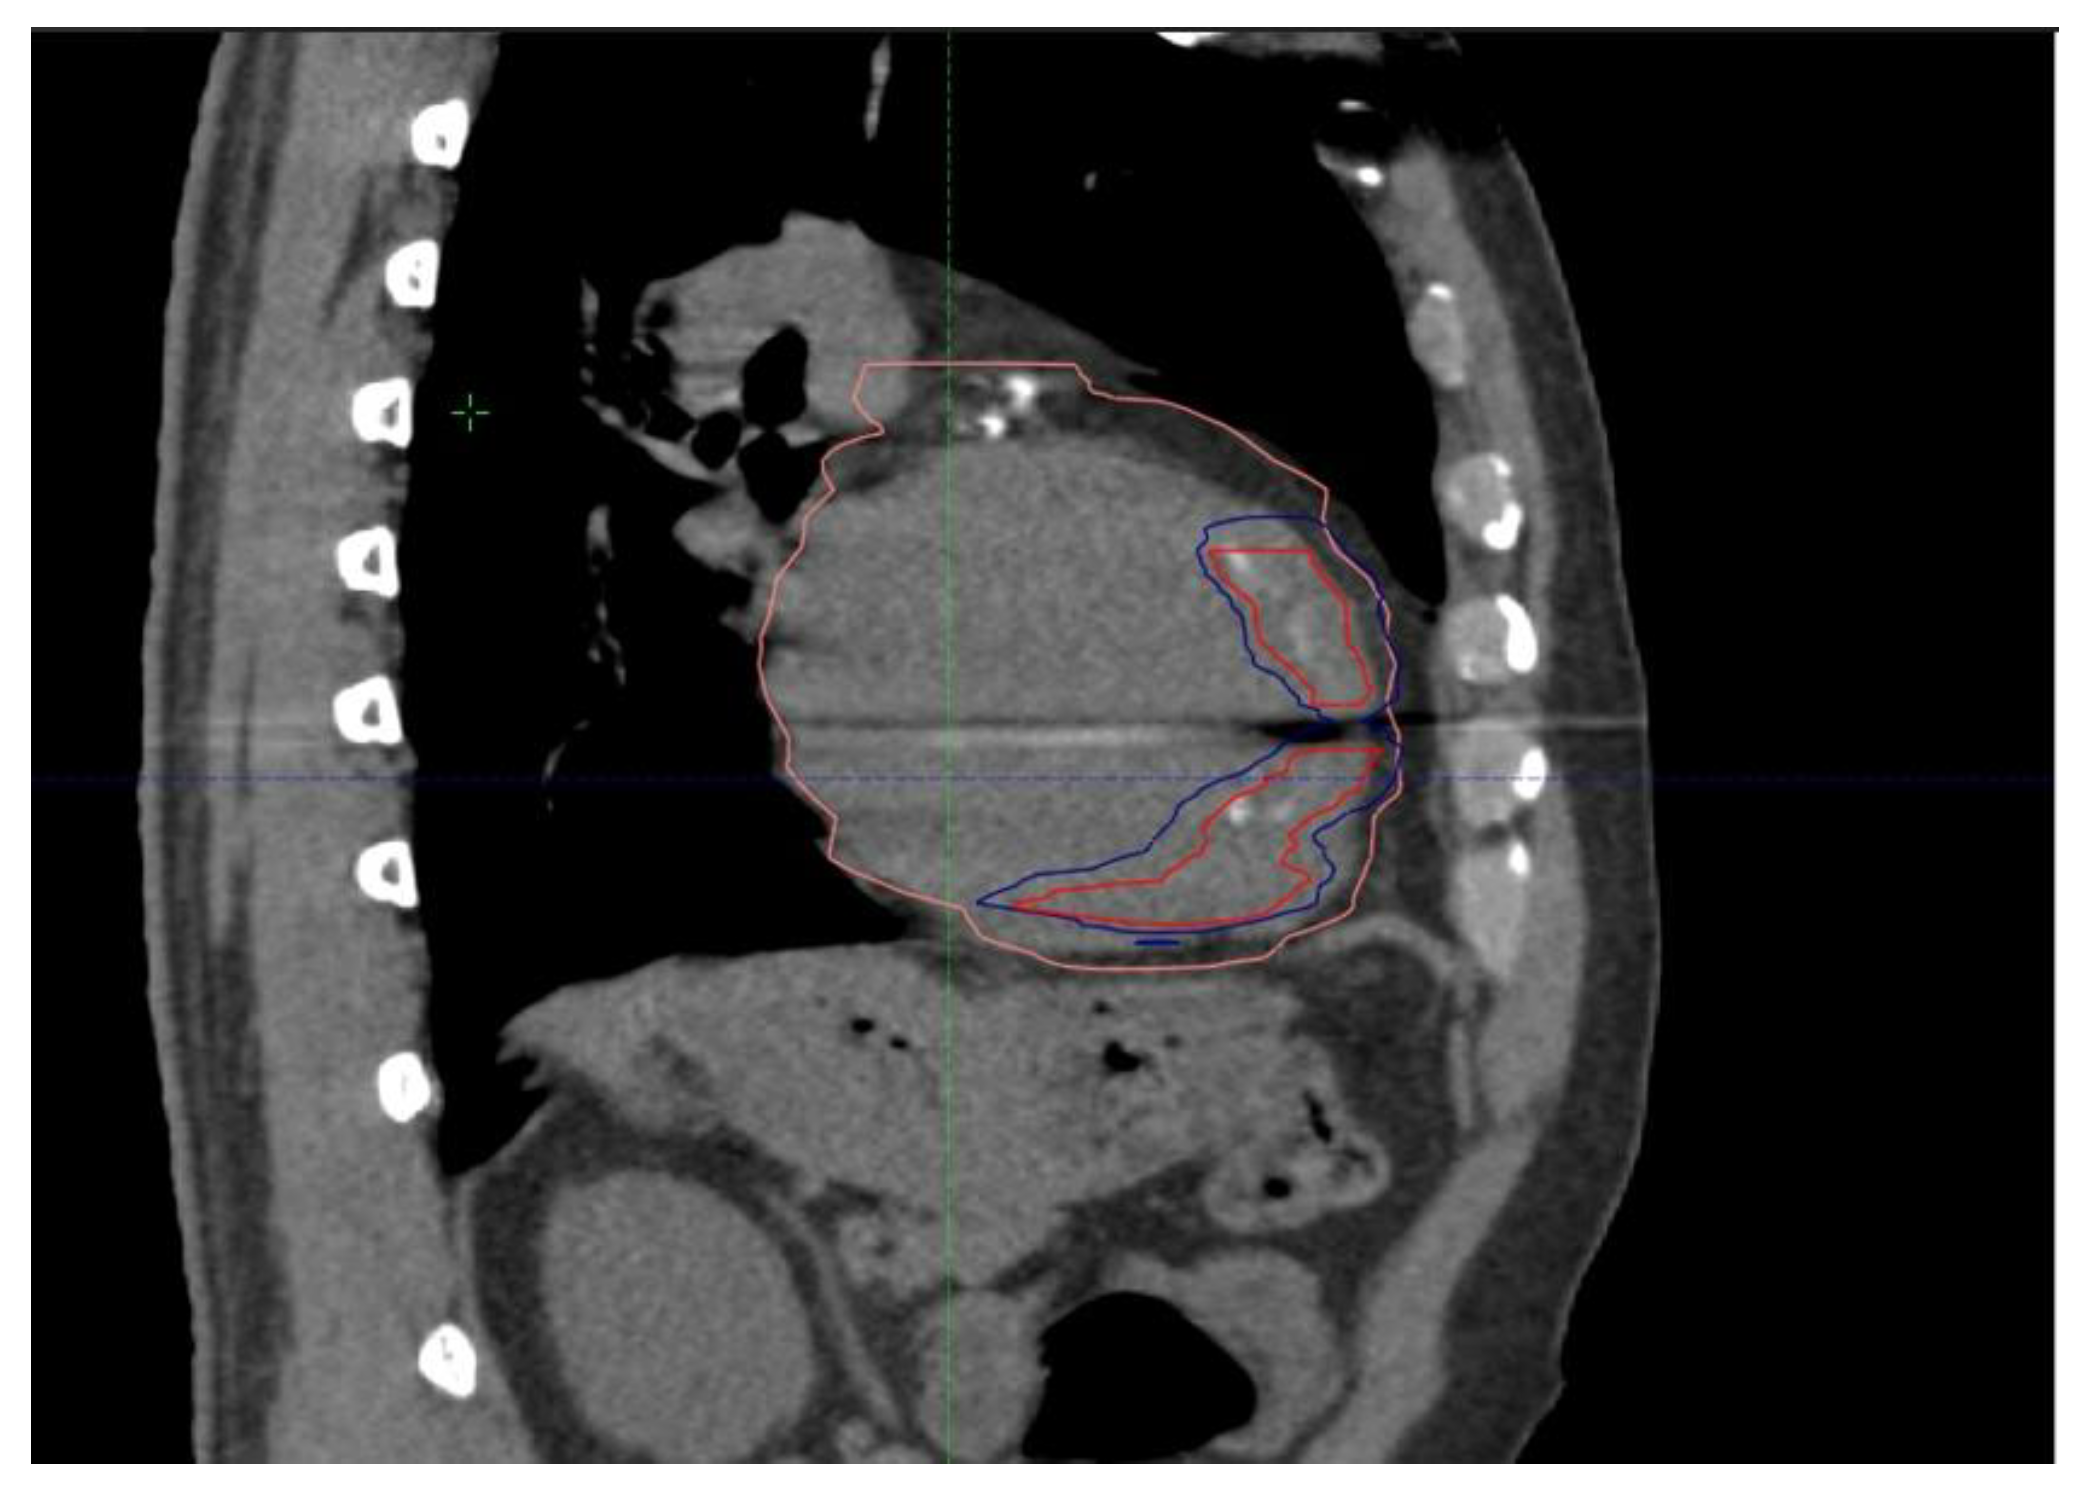

2. Case Presentation